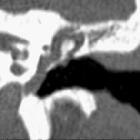

High-resolution temporal bone CT is routinely performed and may show:

- soft tissue density in the middle ear cavity

- thickened tympanic membrane

- bulging tympanic membrane

- tympanic perforation

Features seen in chronic rather than acute otitis media include:

- air-fluid level in the middle ear (effusion)

- bony erosion (less than 10%)

- adjacent sclerosis and hypopneumatisation of the mastoid